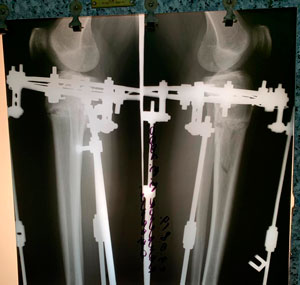

Исходник - 19 лет.

Ротация с обеих сторон.

Дата операции - 17.06.2019г.

Рентген перед снятием аппаратов.